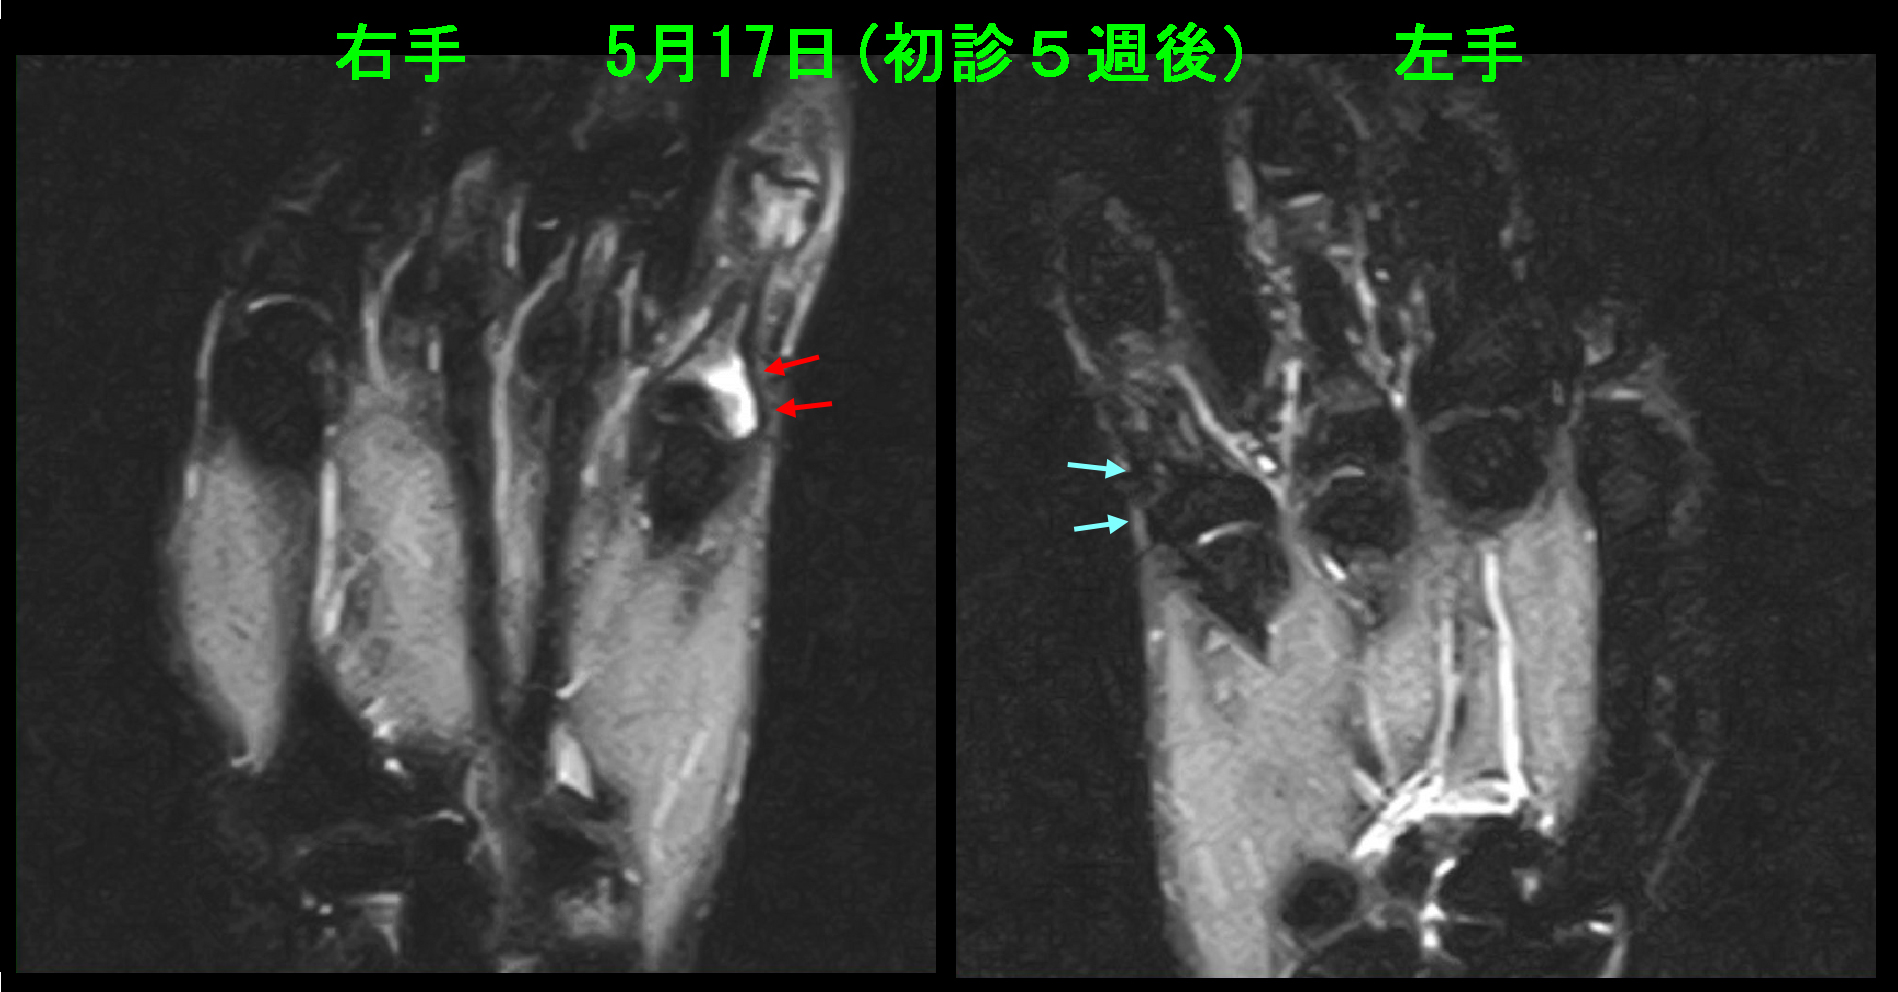

ソフィーMRI検査1.jpg

右小指だけが白くなっています(赤矢印)。この条件で白いのは骨の中に出血している状態と同じです。

ソフィーMRI検査2.jpg

上図で赤矢印が軽微な骨折(赤矢印)となります。最初に提示した75才の女性もこの症例と同じだったのかもしれません。当時はこのような症例にMRI検査を適応するという方針がありませんでした。